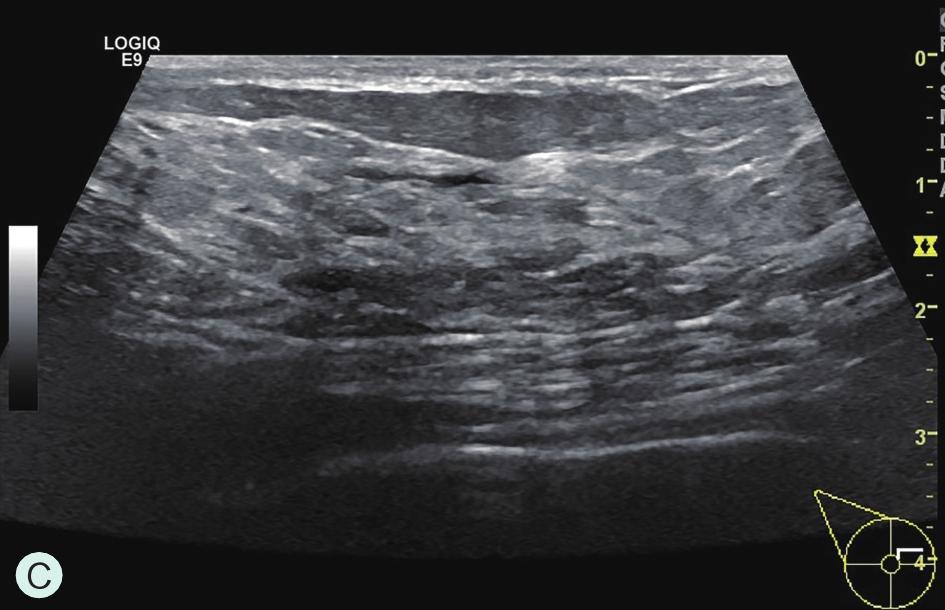

C级:不均匀致密型(可能掩盖小肿块)(图1-3-1C、图1-3-2C、图1-3-3C)。

图1-3-2 乳腺超声不同乳腺密度

A.脂肪型;B.散在致密型;C.不均匀致密型;D.极度致密型